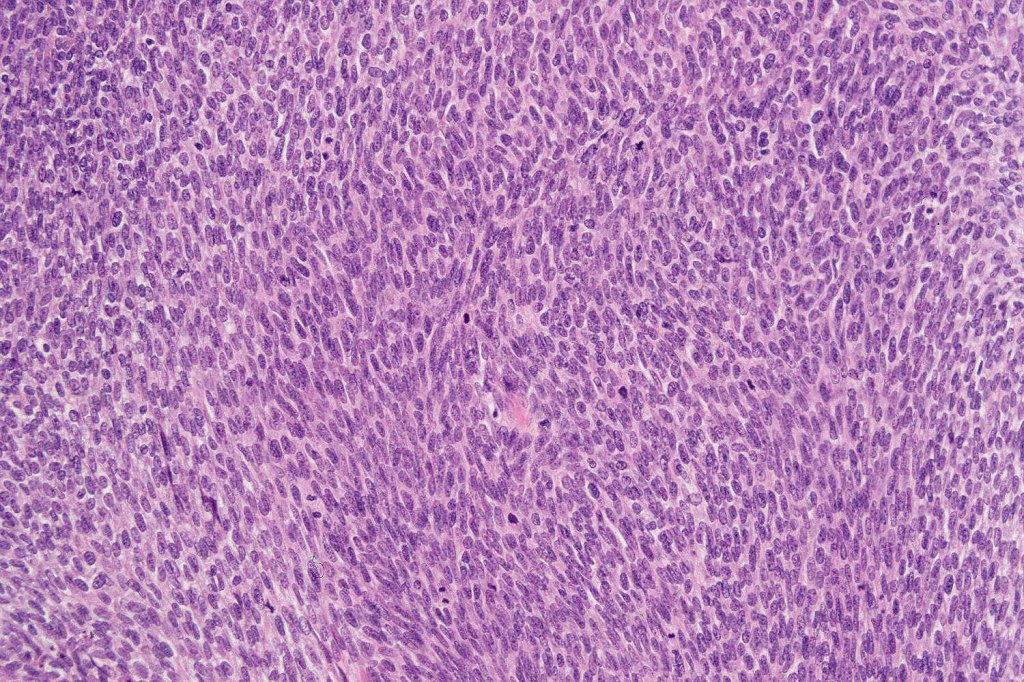

Histological features

•Well differentiated lobular growth pattern though to a poorly differentiated tumor often showing a diffuse, infiltrating border which may extend into the subcutaneous fat

•Tumors are composed of an admixture of darkly staining basaloid cells with hyperchromatic or vesicular nuclei and more obvious sebaceous cells with eosinophilic, bubbly, multivacuolated cytoplasm frequently indenting the nucleus (scalloped)

•Often mitoses are numerous and abnormal forms evident

•Focal squamous differentiation with keratinization can be present resulting in confusion with squamous cell carcinoma

•May be graded into well, moderate & poorly differentiated categories. I am not sure that this has any great value

Sebaceous carcinoma from a patient with Muir-Torre syndrome kindly shared by Dr. Antonina Kalmykova.